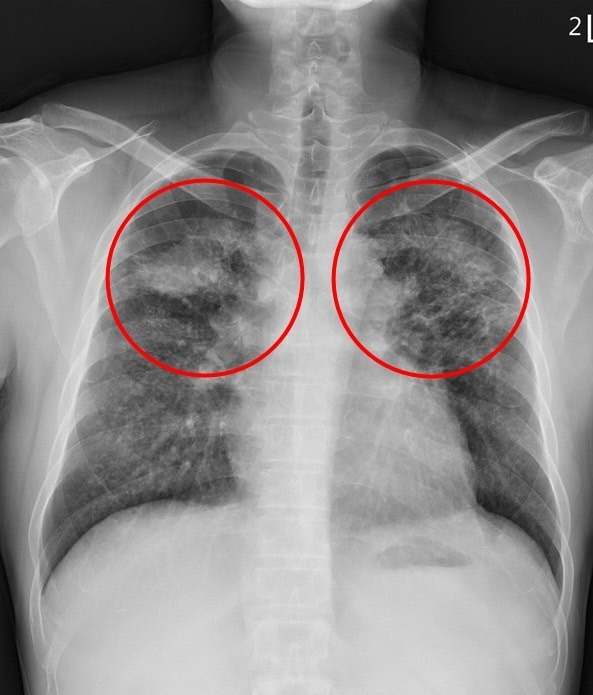

▲ 劉迪塑醫師指出,矽肺症患者的肺部因發炎反應和局部纖維化而產生許多間質性結節,嚴重時甚至會發展為漸進性大量纖維化,在雙上肺葉形成對稱的腫塊。(圖/花蓮慈濟醫院提供)